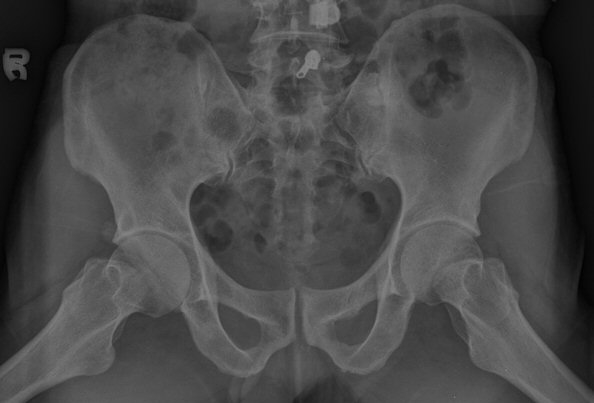

´Ü¼ø¹æ»ç¼±°Ë»ç

ÃÊÁø ½Ã ½ÃÇàÇÑ ¹æ»ç¼± ÃÔ¿µ»ó ÀüÇÏÀ屨 ºÎÀ§¿¡¼­ ¼®È¸È­ À½¿µÀÌ °üÂûµÇ°í, 3ÁÖ ÈÄ ½ÃÇàÇÑ ÃÔ¿µ¿¡¼­

¼®È¸È­ À½¿µ ¼Ò½ÇÀÌ È®ÀεÊ.

Ä¡·á ½ÃÀÛ 1ÁÖ ÈÄ ºÎÅÍ ÅëÁõÀÌ °æ°¨ÇÏ¿´°í 2ÁÖ ÈÄ Áõ»óÀÌ Å©°Ô È£Àü µÇ¾úÀ¸¸ç 3ÁÖ °æ¿¡´Â

Áõ»óÀÌ °ÅÀÇ ¾ø°í ÀÌÇÐÀû°Ë»ç ¼Ò°ßÀÌ Á¤»óÈ­µÇ¾ú°í ¹æ»ç¼± ÃßÀû°Ë»ç¿¡¼­ ¼®È¸È­ ¼Ò½Çµµ

È®ÀεǾú´Ù.